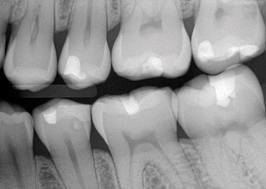

Las radiografías ayudan a estimar la profundidad de

desmineralización por caries en el esmalte y la dentina. La

profundidad no siempre está asociada con la presencia de

cavidad de caries, en especial en superficies proximales.

Investigaciones

clínicas que se realizaron en un país con una tasa baja de

progresión de caries revelaron que, en promedio, el 32% de

las lesiones visibles radiográficamente que se extendían

hasta el tercio externo de la dentina no había cavidad de

caries; por el contario, el 72% de las lesiones que se

extendían hasta 2/3 partes de la dentina tenían cavidad de

caries (33) Las